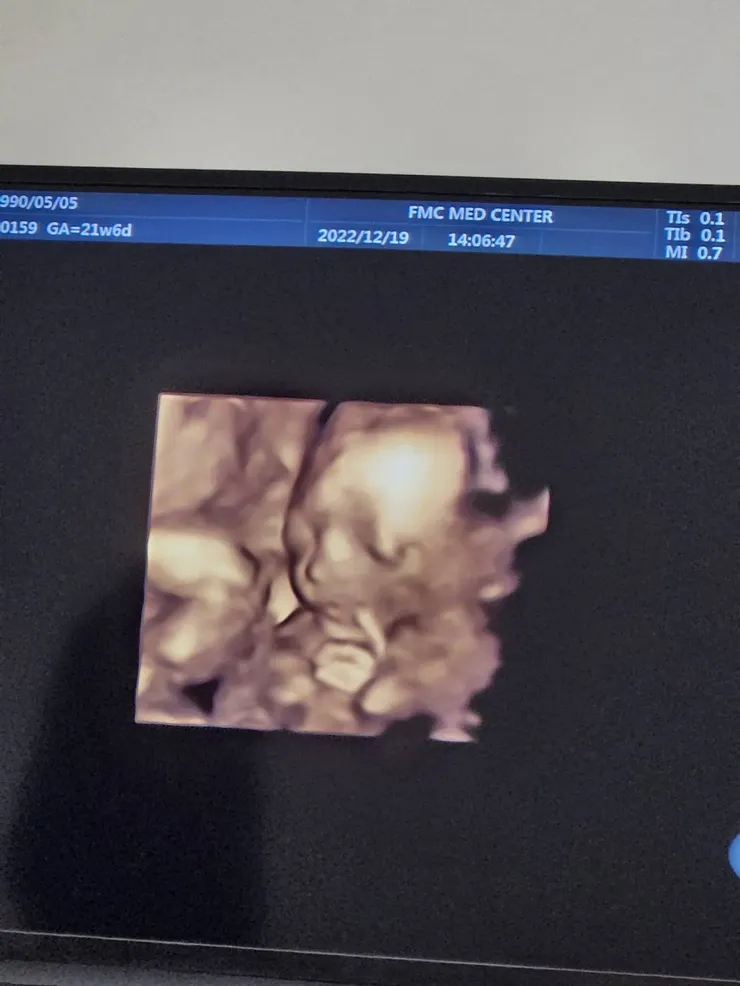

最後~分享一下21週時寶貝的高層次照片~終於等到你~幸福來的好不容易~